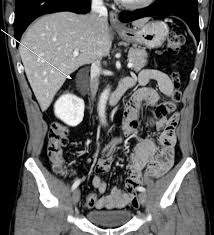

췌장은 소화 효소와 인슐린을 생산하는 장기로, 만약 이 장기에 문제가 생기면 심각한 건강 문제가 발생할 수 있습니다. 췌장염, 췌장암 등은 복부 CT를 통해 손쉽게 진단할 수 있으며, 췌장의 구조와 주변 조직 간의 상호작용을 명확히 확인할 수 있습니다. 특히 췌장암은 조기 발견이 매우 어렵지만, CT를 통해 미세한 종양까지 확인이 가능하므로 결과적으로 치료 효과를 극대화할 수 있습니다.

췌장염은 췌장이 염증으로 인해 기능을 상실하는 질환으로, 주로 알코올 소비와 그에 따른 지방 간섭이 주요 원인으로 알려져 있습니다. 췌장염의 증상으로는 극심한 복통, 구역질 등이 있으며, 이러한 증상을 주의 깊게 살펴보는 것이 중요합니다. 복부 CT 검사는 즉각적인 진단을 통해 적절한 치료 계획을 세우도록 도와줍니다.